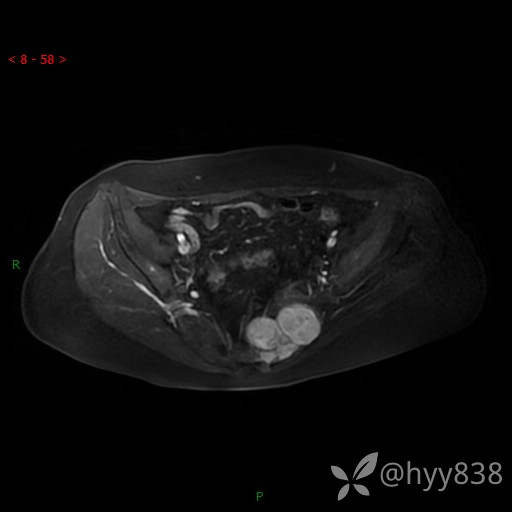

骨盆MRI平扫(T1WI+T2WI+DWI)(外院CT,不能上传)